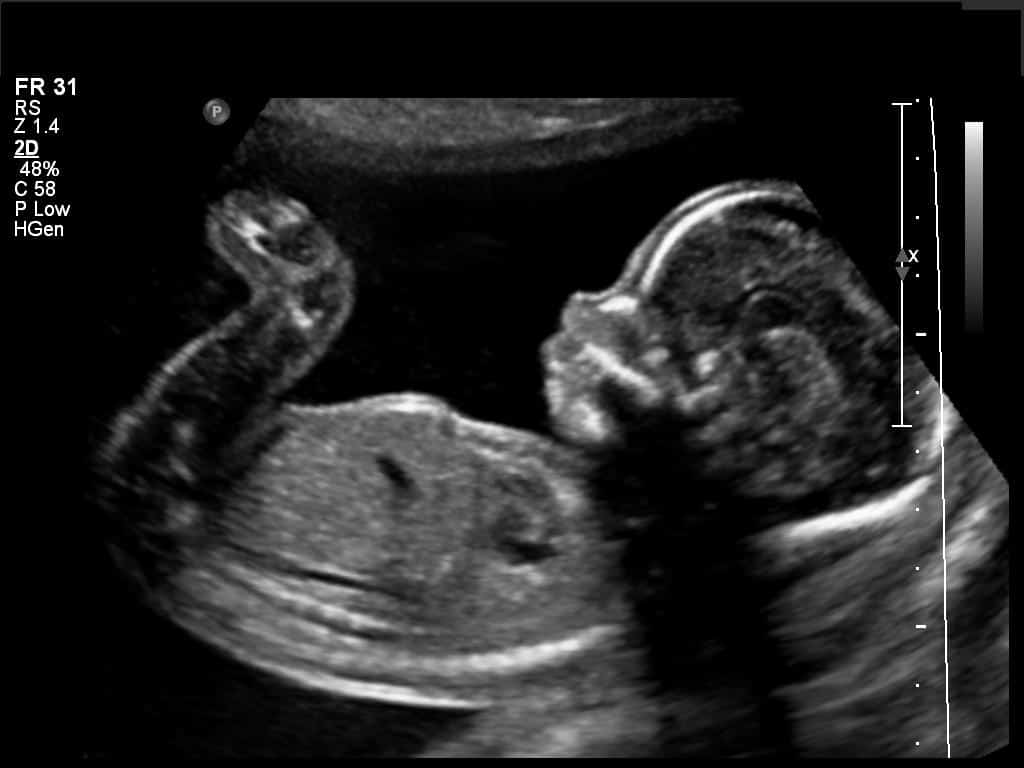

There’s another type of wave used by medical experts, it’s called Ultrasound. This uses sound waves to look inside the body. The sound waves bounce off things like an echo in a cave. Different types of tissue, like fluid, bone or muscle, send back different sounding echoes which are translated into a moving image by a computer. This is essentially the technology used in the coybely pocket doppler, which mothers use to monitor the heart rate of their unborn child.